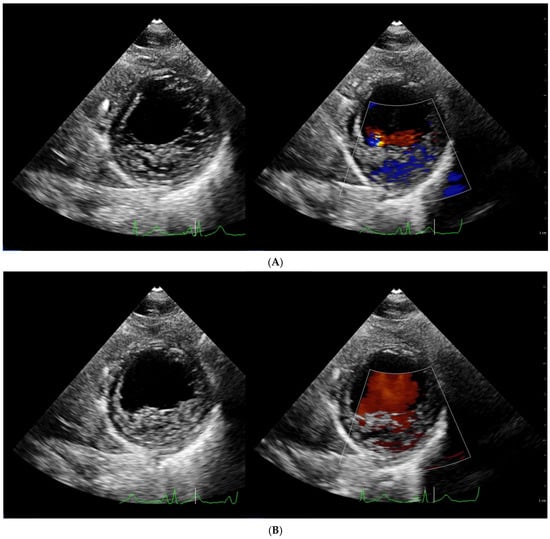

4.1. Echocardiography

| Chin [3] | ECHO | The ratio of the distance from the deepest trabecular recess to the epicardial surface (X) and the distance from the tip of the trabeculation to the epicardial surface (Y) | Long axis, end diastole | X/Y ≤ 0.5 |

| Stöllberger [47] | ECHO | Ratio of compacted and non-compacted endocardium. Presence of at least 3 trabeculations protruding in the left ventricle apically from papillary muscle, presence of the blood flow between trabeculations. | Four chamber, end diastole | NC/C > 2 |

| Jenni [33] | ECHO | Ratio of compacted and non-compacted endocardium. Absence of coexisting cardiac abnormalities, the presence of deep trabeculations, which are filled with blood | Short axis, end systole | NC/C ≥ 2 |